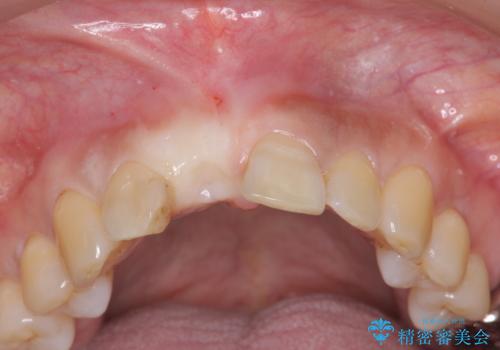

- 前歯を外傷により失い、審美性の改善を求めて来院されました。

横の歯を削る必要のあるブリッジ治療、着脱の必要な入れ歯に強い抵抗があったためインプラント治療を計画します。

審美的・機能的に良好な位置に埋入するには、骨量が十分ではなかったため骨の造成を併用したインプラント埋入外科手術を行います。